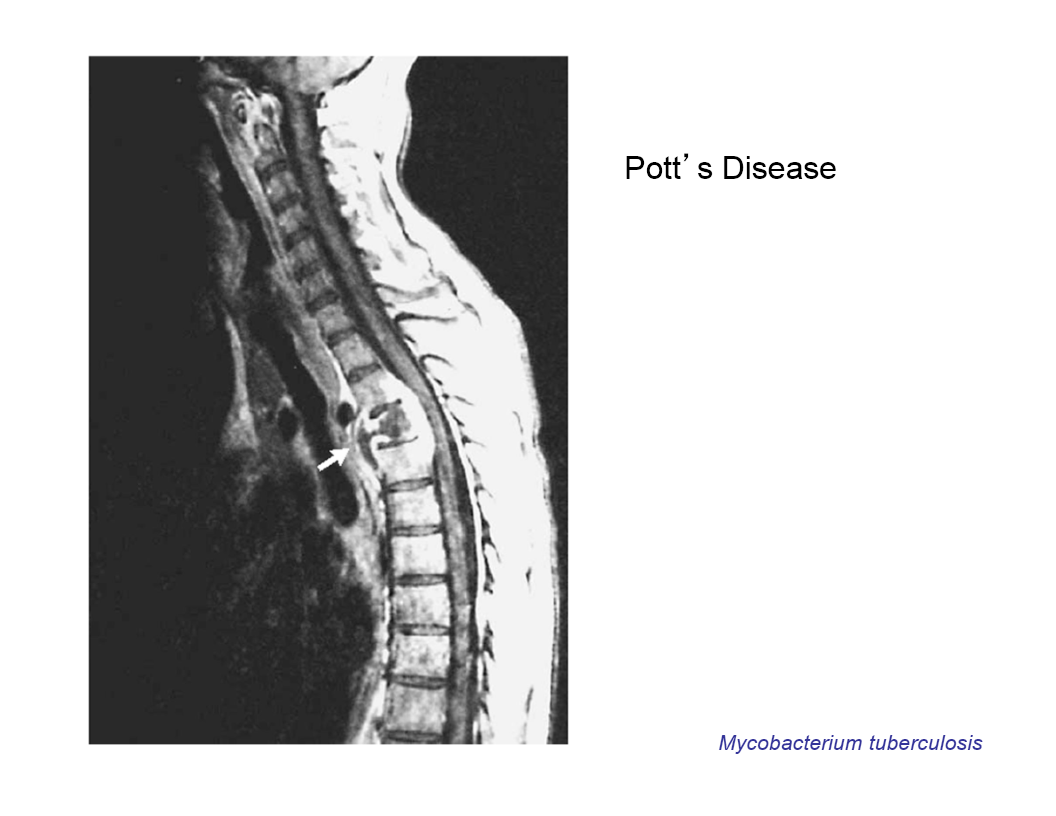

Pott’s DIsease

TB of the spine

extrapulmonary TB:

disease may occur in other organs and sites

lymph nodes, pleura, genitourinary tract, bones and joints, meninges, and peritoneum